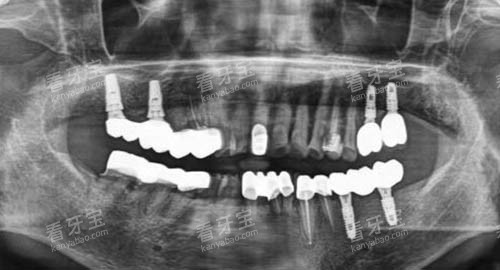

ÑÀ¹Ú£¬Ë׳ơ°ÑÀÌס±£¬ÊǸ²¸ÇÔÚÌìÈ»ÑÀ»òÖÖÖ²ÌåÉϵÄÐÞ¸´Ì壬ÓÃÓÚÐÞ¸´ÑÀ³ÝÍâÐΡ¢¹¦Äܼ°ÃÀ¹Û¡£³£¼ûÓÚÒÔÏÂÇé¿ö£º¸ù¹ÜÖÎÁƺóÑÀ³Ý±ä´à¡¢ÖصÄÈ£»µÎÞ·¨²¹ÑÀ¡¢ÍâÉ˵¼ÖÂÑÀÌåȱËð¡¢ÑÀ³ÝÑÕÉ«ÐÎ̬Òì³£ÐèÃÀѧ¸ÄÉÆ£¬»ò×÷ΪÖÖÖ²ÑÀµÄ½ÏÖÕÐÞ¸´²¿·Ö¡£

ÖÖÖ²ÌåÉϲ¿È«´É¹Ú£¨µ¥¿Å£©£º1980ÔªÆð£¨Èç´îÅäµÇÌÚÖÖÖ²Ì壩